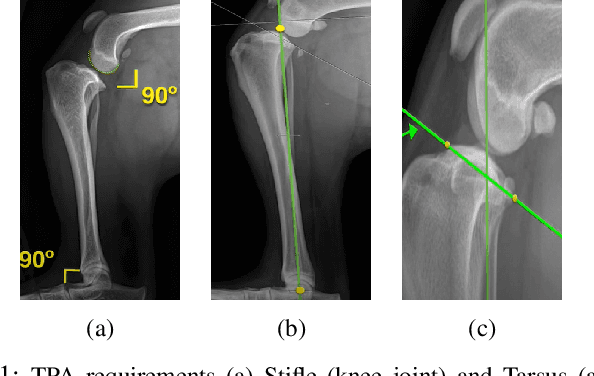

Abstract:Stifle joint issues are a major cause of lameness in dogs and it can be a significant marker for various forms of diseases or injuries. A known Tibial Plateau Angle (TPA) helps in the reduction of the diagnosis time of the cause. With the state of the art object detection algorithm YOLO, and its variants, this paper delves into identifying joints, their centroids and other regions of interest to draw multiple line axes and finally calculating the TPA. The methods investigated predicts successfully the TPA within the normal range for 80 percent of the images.